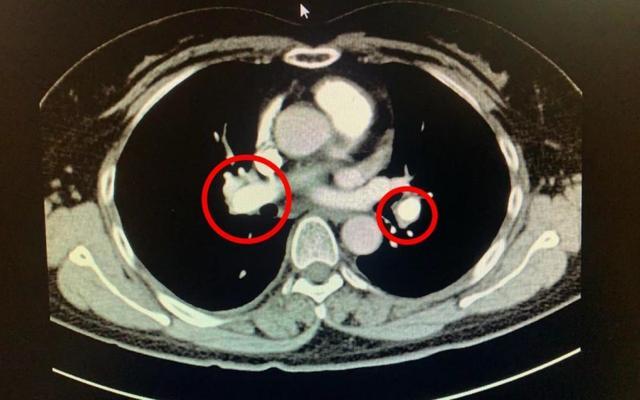

2天后,复查CT,提示肺动脉供血恢复,病情稳定后转普通病房,创口感染控制即行二期清创缝合,同时继续预防血栓再次形成。

(▲肺动脉增强剂充盈良好,未见缺损)